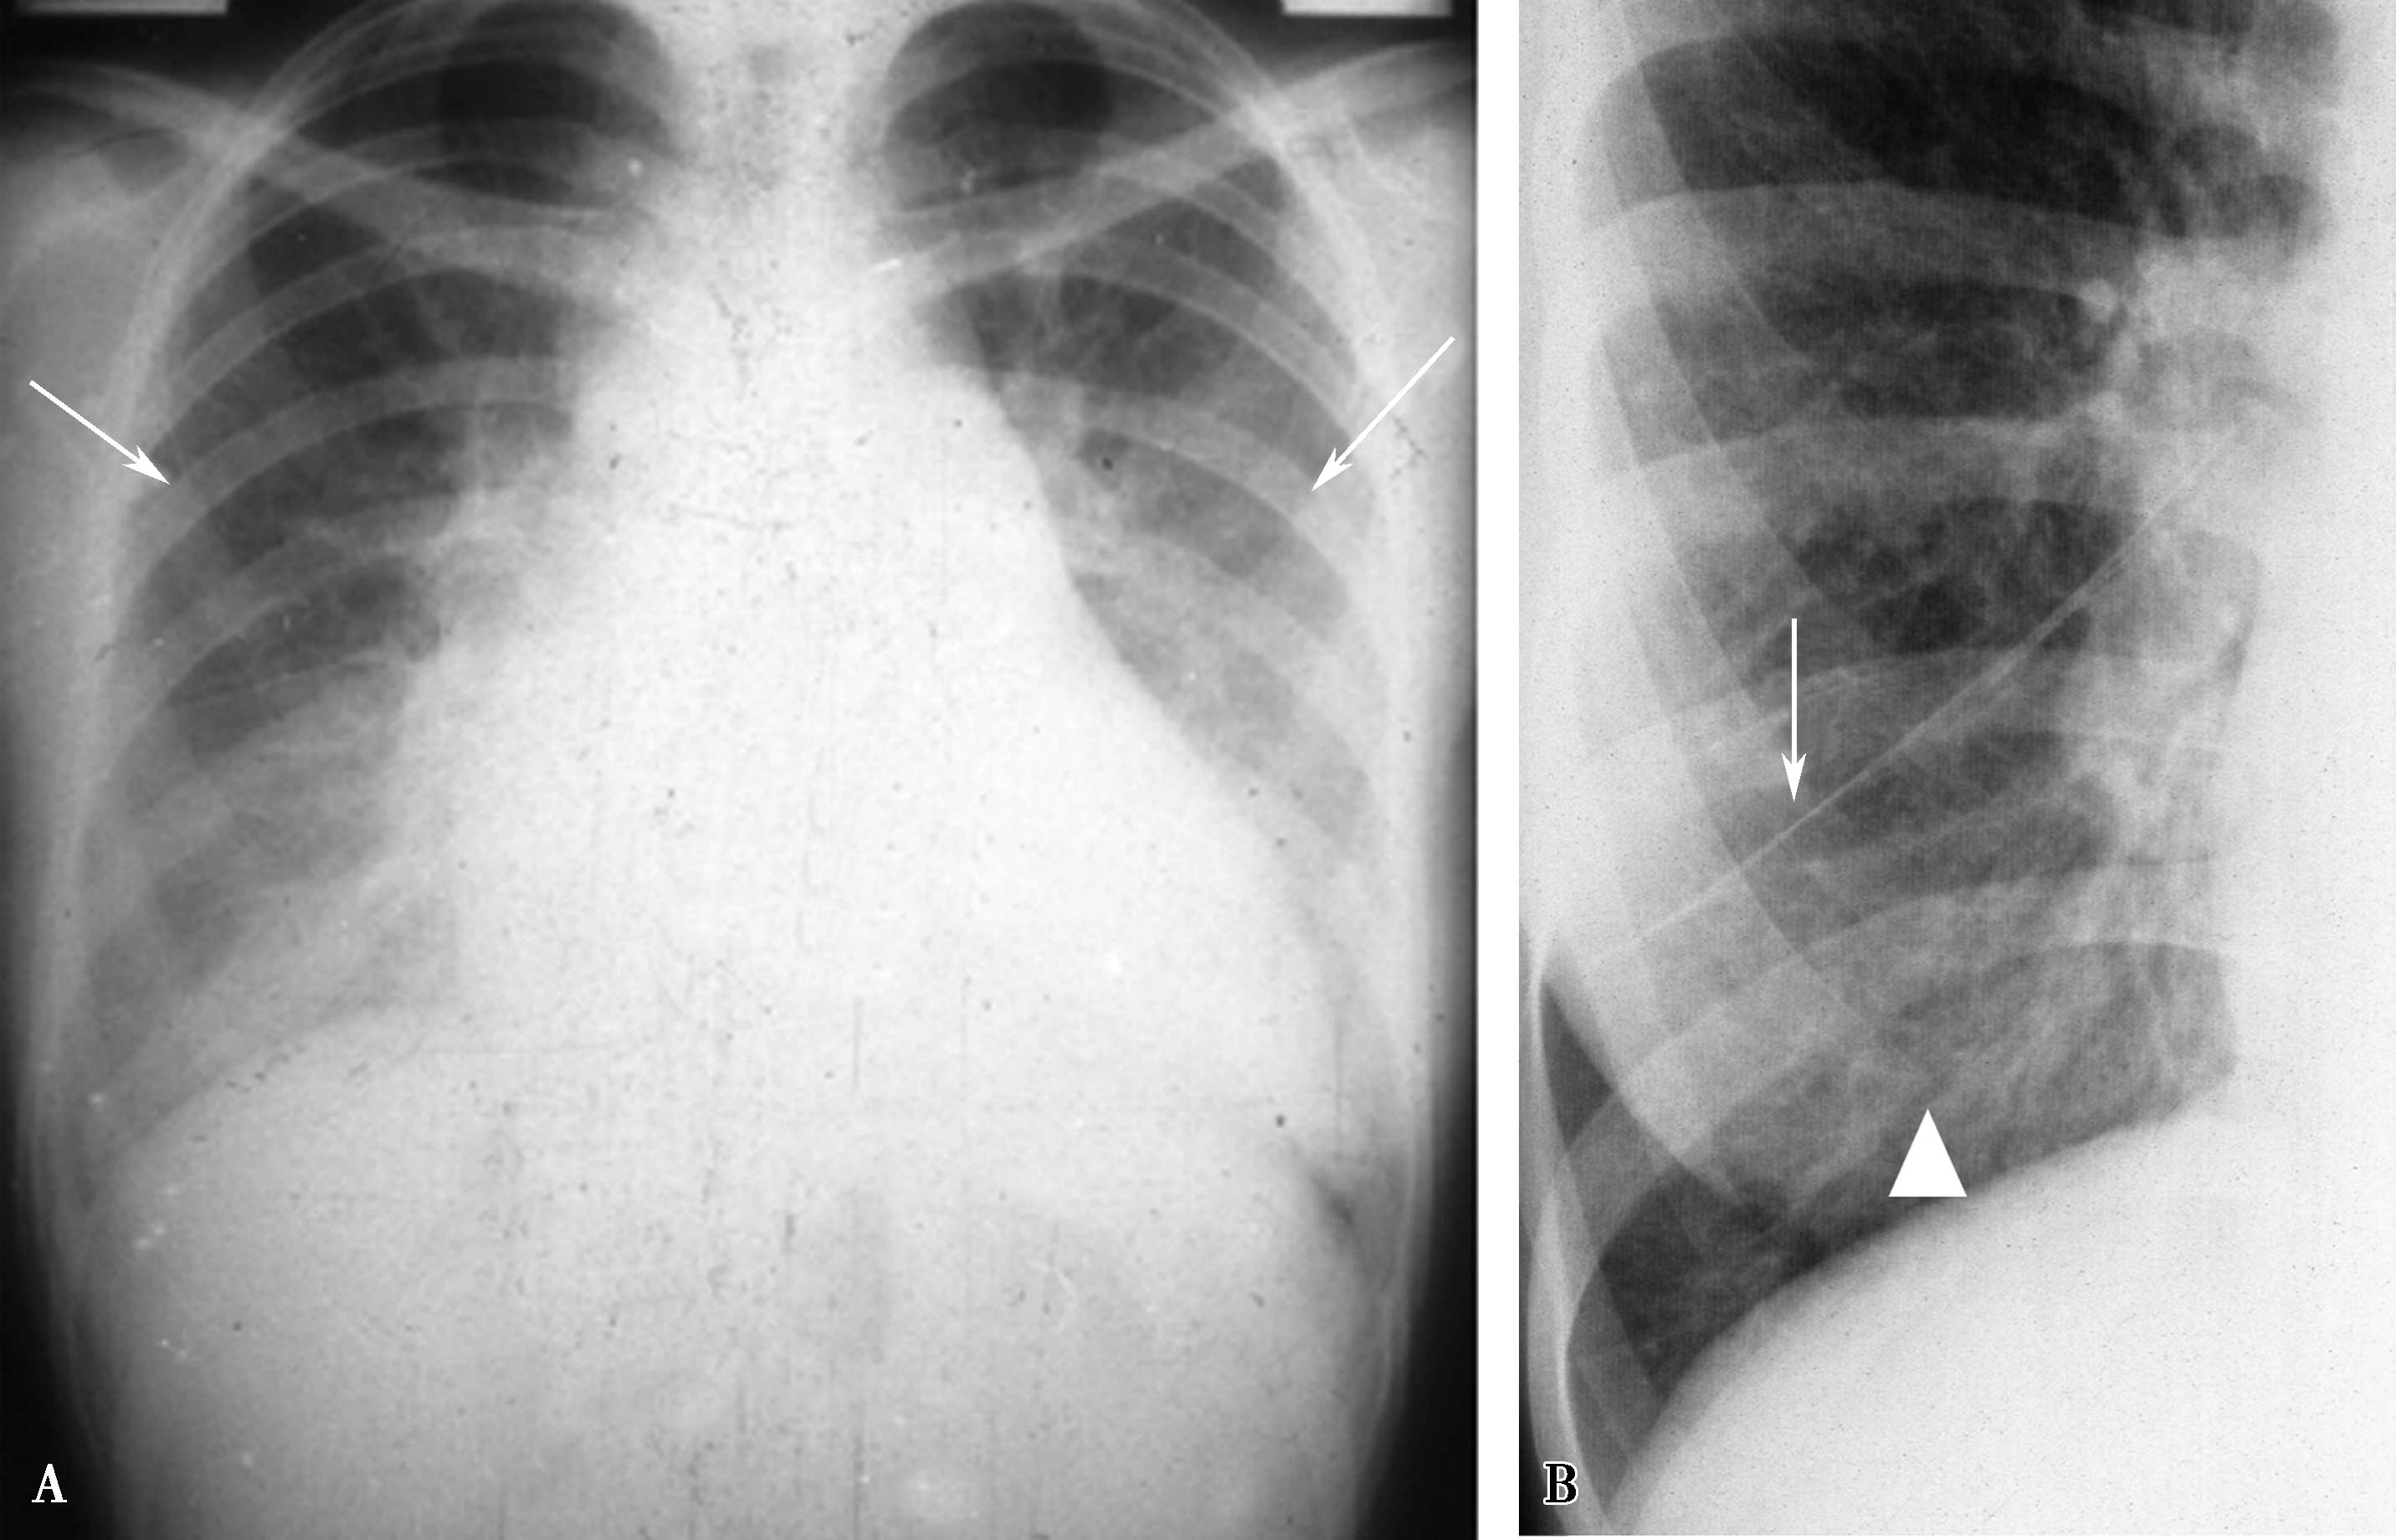

2.先天性一侧肺动脉缺如(图7-2-5)

图7-2-5 男,20岁,先天性一侧肺动脉缺如 右侧肺透过度增高,肺血明显减少(▲)。右膈升高(↑),右肺容积减小;右心增大,肺动脉高压